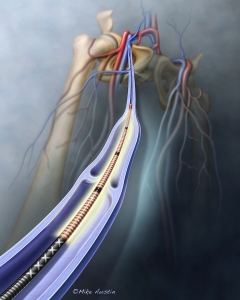

Internal Art Medical Illustration

Blending Art, Anatomy and Science for Creative Visuals

Patient & Professional Marketing

Welcome to my Patient and Professional Marketing page, where I harness the power of anatomical illustrations to educate and empower both patients and medical professionals. My unique approach combines artistry and education to convey complex surgical procedures and the utilization of medical devices in an easily understandable manner.